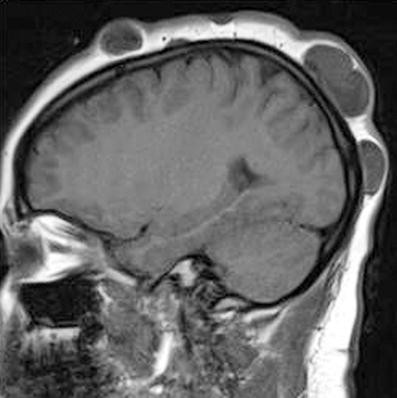

• Cortical tubers

• Associated with developmental delay and seizures

• Subependymal nodules (SENs)

• May calcify over time

• Subependymal giant cell astrocytomas (SEGAs)

• Can cause hydrocephalus

• Brain MRI

• Neurological manifestations:

• Seizures